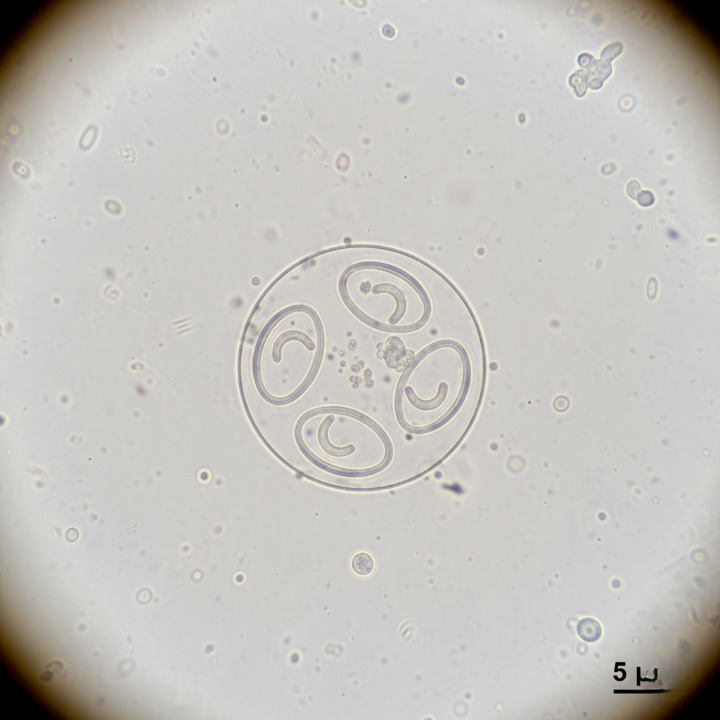

Eimeria ovis → causa cuadros clínicos y se identifica por presentar un casquete (estructuras morfológicas reconocibles en el ooquiste).

Eimeria ovinoidalis y Eimeria crandallis